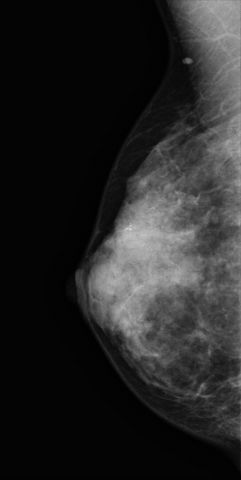

A més donada la posició que la pacient ha de mantindre durant l'examen, hi ha la possibilitat que el protector de tiroides interfereixi creant artefactes en la imatge, que poden afectar a la qualitat de la mateixa , per tant, a un correcte diagnostic. Això podria, fins i tot, fer necessària la repetició de la mamografia, implicant un increment injustificat en la dosis rebuda per la pacient.

Sobre la base d'aquest fet exposat es considera que durant la realització de la mamografia no es necessari utilitzar el protector plomat de tiroides, i el seu ús pot ser perjudicial per la pacient des del punt de vista del correcte diagnostic i de la optimització de la protecció radiològica.